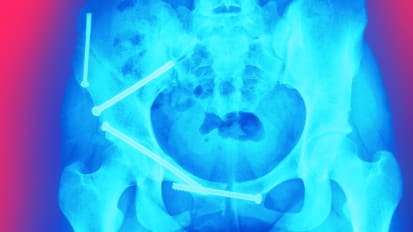

UTSW earns distinction for hip fracture performance

Hip fractures are a major health concern for older people – those age 65 and over – especially for women, according to the Centers for Disease Control and Prevention (CDC).